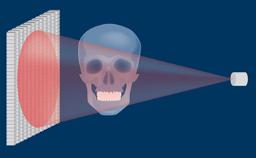

O sucesso do tratamento com implantes requer um plano com orientação protética para determinar a posição ideal do implante. A posição do implante deve facilitar a instalação de uma prótese definitiva ideal que atenda às exigências funcionais e estéticas e mimetize a dentição natural.

Usando investigações diagnósticas adicionais, os requisitos cirúrgicos e protéticos específicos da região podem ser identificados e avaliados. Isso ajuda a minimizar o risco de complicações e falhas após o tratamento com implantes.